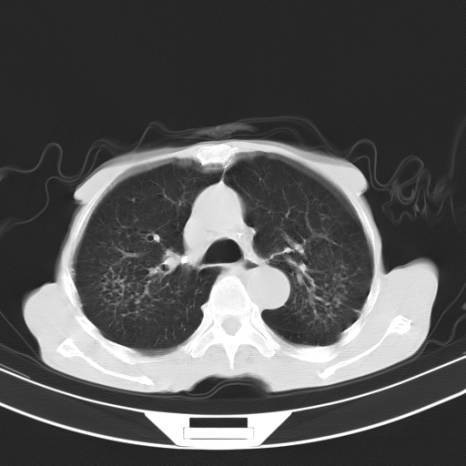

ct诊断肺结核宝典:这是我见过的最好的经验总结!

图丨肺结核的ct表现

透视结论为陈旧性肺结核,近日复查cr,发现右肺门结构紊乱,遂做ct检查